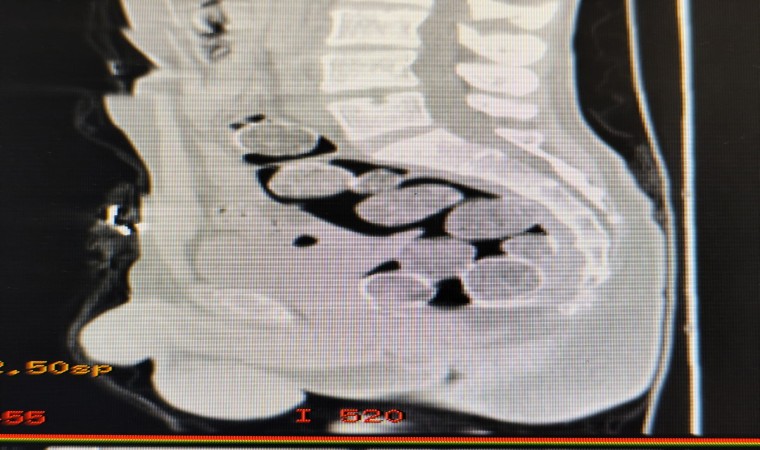

Samsun’a yutarak uyuşturucu madde sokmak isteyen 2 kişi ile onları otogarda karşılayan şahıs, polisin operasyonu sonucu yakalandı. Samsun Cumhuriyet Başsavcılığı koordinesinde, uyuşturucu madde ticareti yapan şahıslara yönelik yapılan çalışmalarda İl Emniyet Müdürlüğü Narkotik Suçlarla Mücadele Şube Müdürlüğü ekipleri, Samsun’a uyuşturucu naklettiğinden şüphelenilen ve Samsun otogarına gelen A.A(36) ve H.T.’yi (44) takibe aldı. Şahısların binmiş olduğu araç İlkadım ilçesi Kıran Mahallesi’nde durduruldu. Araçta bulunan şahıslar ve araç üzerinde yapılan aramada herhangi bir uyuşturucu madde bulunamadı. Şahısların yanlarında valiz, çanta veya eşya bulunmaması ve A.A. ve H.T.’nin halsiz, tedirgin ve şüpheli davranışlar sergilemeleri üzerine yutmak suretiyle bağırsaklarında ve midelerinde uyuşturucu maddeyi getirebileceği değerlendirilerek, Samsun Eğitim ve Araştırma Hastanesine sevklerine karar verildi. Hastanede çekilen röntgen filminde, mide ve bağırsaklarında yabancı maddeler olduğu tespit edilen A.A. ve H.T. gözaltına alındı.

A.A. ve H.T.’nin mide ve bağırsaklarına yapılan tıbbi müdahale sonucunda, 18 paket halinde toplam 500 gram metamfetamin ele geçirildi. Şüpheli şahısların ikametlerinde yapılan aramada ise 1 adet ruhsatsız tabanca ve 99 adet fişek elde edildi. A.A. ve H.T.’nin yanı sıra onlara yardım ve yataklık ettiği tespit edilen R.K.(44) de polis ekiplerince gözaltına alındı.